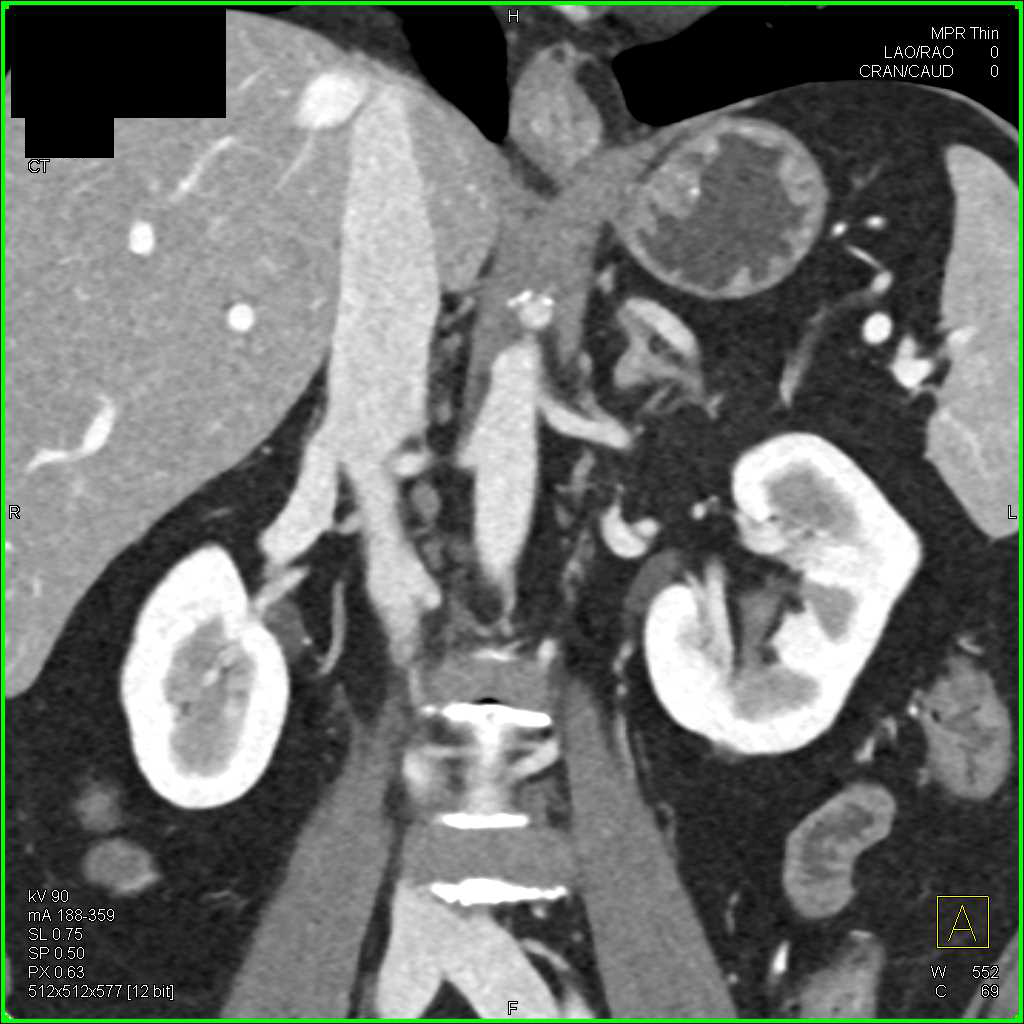

Leak from Urethra Post Prostatectomy with CT Cystogram